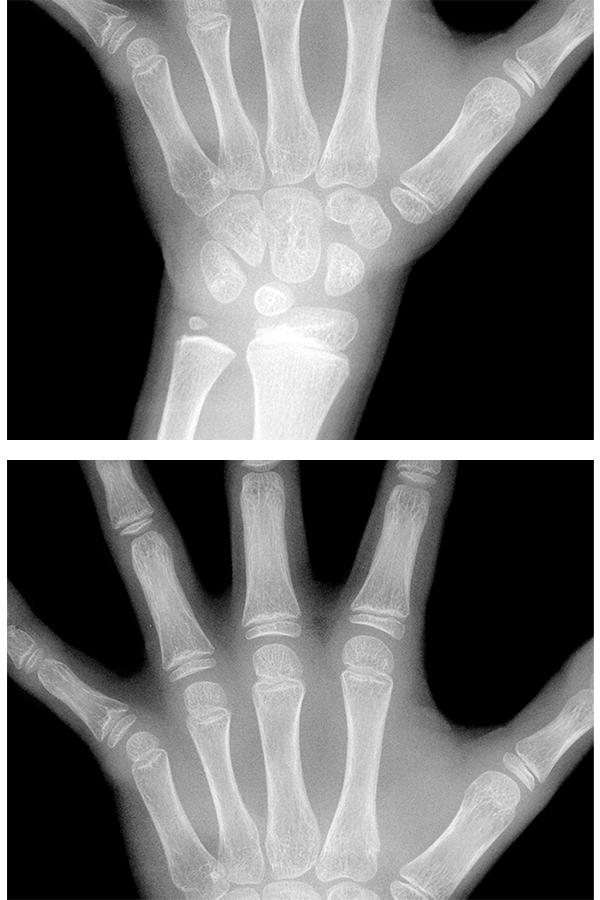

성장판, 골연령 검사 및

성장 예측키 분석

성장판 상태를 분석하여 아이의 뼈 나이를 측정, 현재 나이와 비교해 성장이 빠른지 늦은지 진단하며 어느정도 성장할 수 있는지 예상 할 수 있습니다.